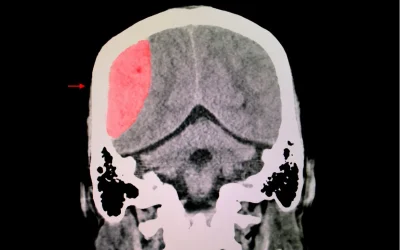

Hyperbaric Oxygen Therapy Can Induce Angiogenesis and Regeneration of Nerve Fibers in Traumatic Brain Injury Patients

Background: Recent clinical studies in stroke and traumatic brain injury (TBI) victims suffering chronic neurological injury present evidence that hyperbaric oxygen therapy (HBOT) can induce neuroplasticity. Objective: To assess the neurotherapeutic effect of HBOT on...

Breathing Pure Oxygen Could Repair Brain Damage Years After a Concussion

In Brief Researchers from Tel Aviv University have shown that treating post-concussion syndrome patients with pure oxygen helps to regrow blood vessels and nerve endings. This could help to alleviate cognitive symptoms ranging from headaches to mood changes. Brain...

Hyperbaric Oxygen Therapy for Post-Concussion Syndrome

A recent study conducted by Wolf and associates1 has stirred the waters, prompting a closer examination of its conclusions regarding Hyperbaric Oxygen Therapy (HBOT) for the treatment of mild traumatic brain injury (mTBI)/post-concussion syndrome (PCS) and...

Hyperbaric Oxygen Therapy (HBOT) for Traumatic Brain Injury and PTSD

In recent years, there has been growing interest in the potential of Hyperbaric Oxygen Therapy (HBOT) as a treatment for conditions like traumatic brain injury (TBI) and post-traumatic stress disorder (PTSD). A recent study sheds light on the promising results of HBOT...